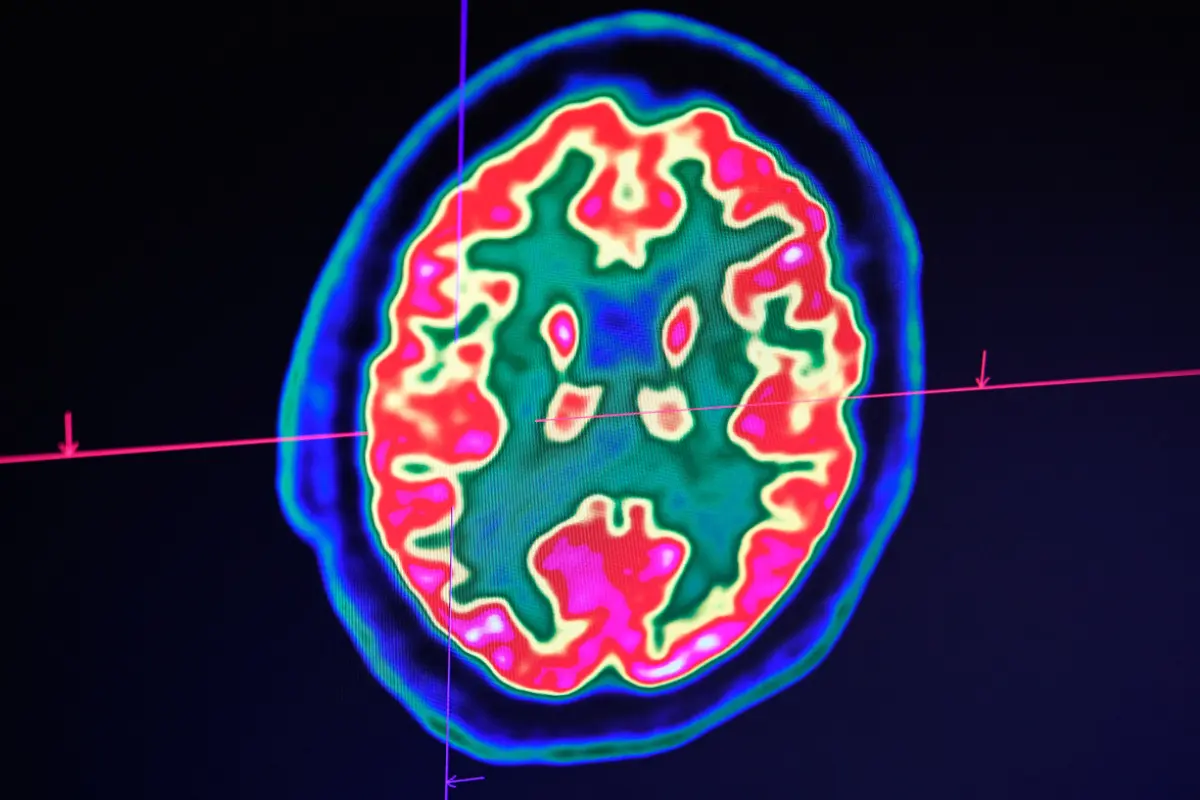

Etwa die Hälfte trage bleibende Schäden wie Lähmungen oder Sprachstörungen davon, wurde Christian Tackenberg, wissenschaftlicher Abteilungsleiter in der Gruppe Neurodegeneration am Institut für Regenerative Medizin der Universität Zürich (UZH), in einer Medienmitteilung vom Dienstag zitiert. Durch Einblutungen oder mangelnde Sauerstoffversorgung sterben Hirnzellen unwiederbringlich ab. Zurzeit existiere keine Behandlung, um solche Schäden zu reparieren.

Das Potenzial dazu haben nun laut der UZH neuronale Stammzellen. Die Studienresultate zeigten, dass neuronale Stammzellen nicht nur neue Nervenzellen ausbilden, sondern auch weitere Regenerationsprozesse in Gang setzen, wie ein Team um Tackenberg und Postdoktorandin Rebecca Weber in Kollaboration mit der University of Southern California in zwei Studien belegt. So bilden die transplantierten Zellen neue Nervenzellen, fördern die Regeneration von Blutgefäßen, reduzieren Entzündungen und verbessern die Blut-Hirn-Schranke, wie es weiter hieß.

Für die Studie kamen menschliche neuronale Stammzellen zum Einsatz, aus denen sich unterschiedliche Zelltypen des Nervensystems bilden können. Für die Untersuchung lösten die Forschenden einen permanenten Schlaganfall in Mäusen aus, dessen Merkmale einem Hirninfarkt beim Menschen stark ähneln. Die Tiere waren genetisch so modifiziert, dass die menschlichen Stammzellen nicht abgestoßen wurden.

Eine Woche nach dem Schlaganfall transplantierte das Team die neuronalen Stammzellen in die betroffenen Hirnregionen. "Erfreulicherweise machte die Stammzelltransplantation bei den Mäusen auch die motorischen Einschränkungen rückgängig, die der Schlaganfall verursacht hatte." Trotz der positiven Resultate gebe es aber noch einiges zu tun, so Tackenberg. Man müsse die Risiken minimieren und eine potenzielle Anwendung im Menschen vereinfachen.